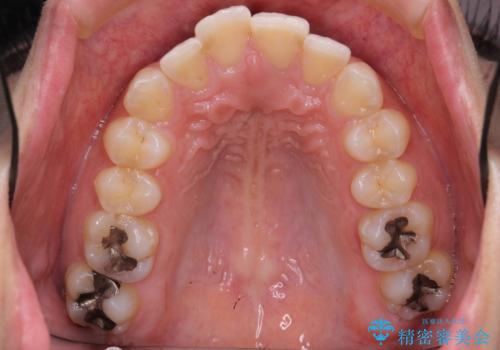

- 治療計画

- 前歯を下げたいと来院。

初めは、上だけ抜歯しましたが、もう少し口元を下げたいとのことで追加で下顎を抜歯しました。

年齢の割に歯が動きにくかったこともあり、また、追加で抜歯して結果として時間がかかってしまいました。口元が大きく下がり、結果には満足していただけました。

横顔が大きく変わり、満足していただけました。